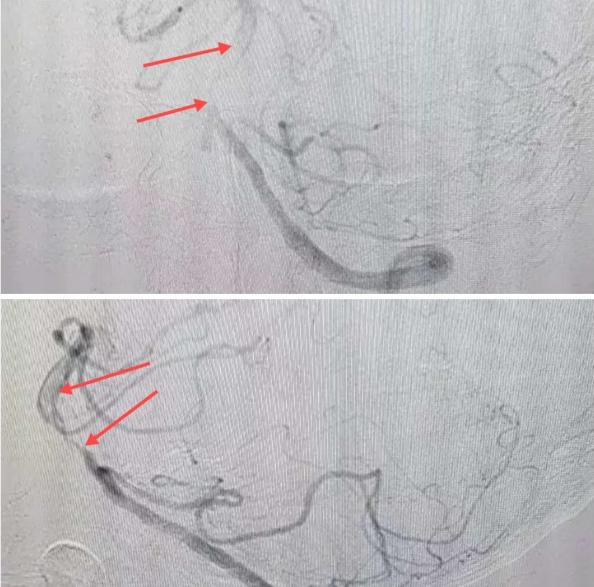

在經(jīng)造影后,主刀醫(yī)生腦一科副主任楊慶堂發(fā)現(xiàn)患者基底動脈下段重度狹窄且狹窄段以遠有大負荷血栓,其狹窄處考慮為動脈夾層,手術難度及風險較大。楊慶堂副主任在彭壯副主任醫(yī)師的協(xié)助下運用spaceman(太空人)技術,中間導管抵近血栓抽吸配合支架拉栓,成功開通血管。再次造影可見基底動脈管腔明顯增寬,遠端血管顯影良好,且等待20分鐘后造影仍顯示血流通暢。楊慶堂副主任考慮到本次手術時間不宜過長,現(xiàn)患者基底動脈及分支前向血流維持良好,給予其抗栓藥物應用后結束手術,并建議患者3個月后復查造影,明確其基底動脈夾層情況。

造影可見血管夾層和大量血栓形成

取栓后血管管腔增寬,前向血流良好